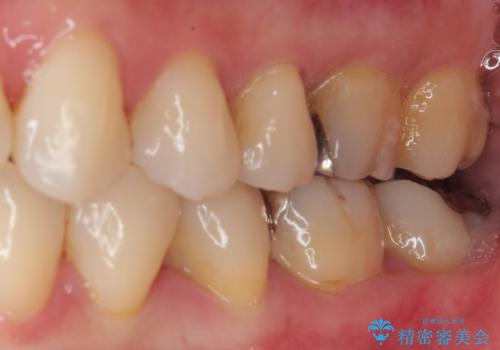

特に異常もなく見た目、噛み合わせともに満足していただけました。

歯と歯の間の虫歯をコンポジットレジンや保険のメタルインレーで治すと段差ができたりして清掃性が悪くなるので、セラミックインレー修復やゴールドインレー修復などの適合の良い詰め物で治療することをオススメします。